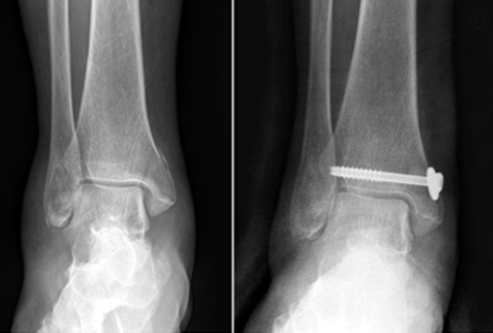

치료의 방침은 크게 도수 정복 후 고정을 통한 비수술적 방법과 관혈적 정복 및 내고정을 통한 수술적 방법으로 크게 나눌 수 있습니다.

비수술적 방법은 대게 전위가 없는 내과나 외과의 단독 골절에서, 또는 수술적 치료를 요하나 환자의 나이나 전신 상태가 수술을 시행하기에 어려운 경우 선택을 하게 되며, 대게 6에서 8주 동안 부목, 석고붕대 등의 고정을 통하여 골절의 유합을 되게 합니다.

그러나, 대부분의 양과 골절이나 삼과 골절은 전위되어 있으며, 이를 마취없이 도수 정복하기는 어렵고, 수술적 가료를 시행하게 됩니다. 골절 후 시간이 지날수록 부종이 심해지고 골다공증이 진행되므로 환자의 상태가 허락한다면, 가능한 수술을 빨리 시행하는 것이 좋습니다. 단, 혈성 수포나 심한 부종이 있는 경우 수술을 연기하는 것이 바람직합니다. 예정된 수술창 부위에 발생한 수포의 경우 터지지 않기까지는 감염성이 없으며, 이에 대한 처치로 저절로 소실될 때까지 기다리거나, 심한 경우 괴사 조직 제거술 후에 치유되고 나서 수술을 시행합니다.